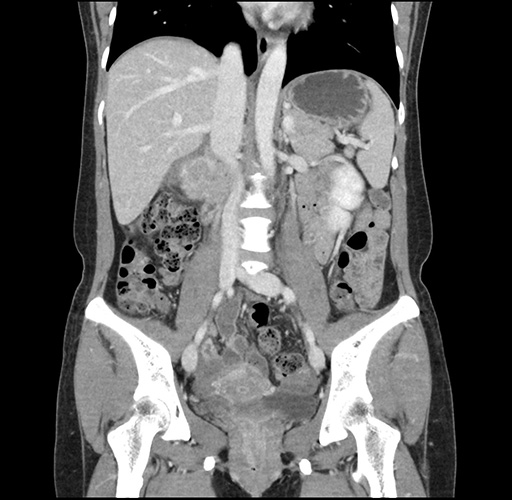

Imaging Analysis

Look through the patient's CT scan to identify any areas of concern for the necessary procedure.

Based on your CT findings, which issue(s) would give reason for "planned slowing down moment(s)" in this case?

Considering a standard left lateral sectionectomy procedure, what step(s) of the operation would you do differently in this case ?